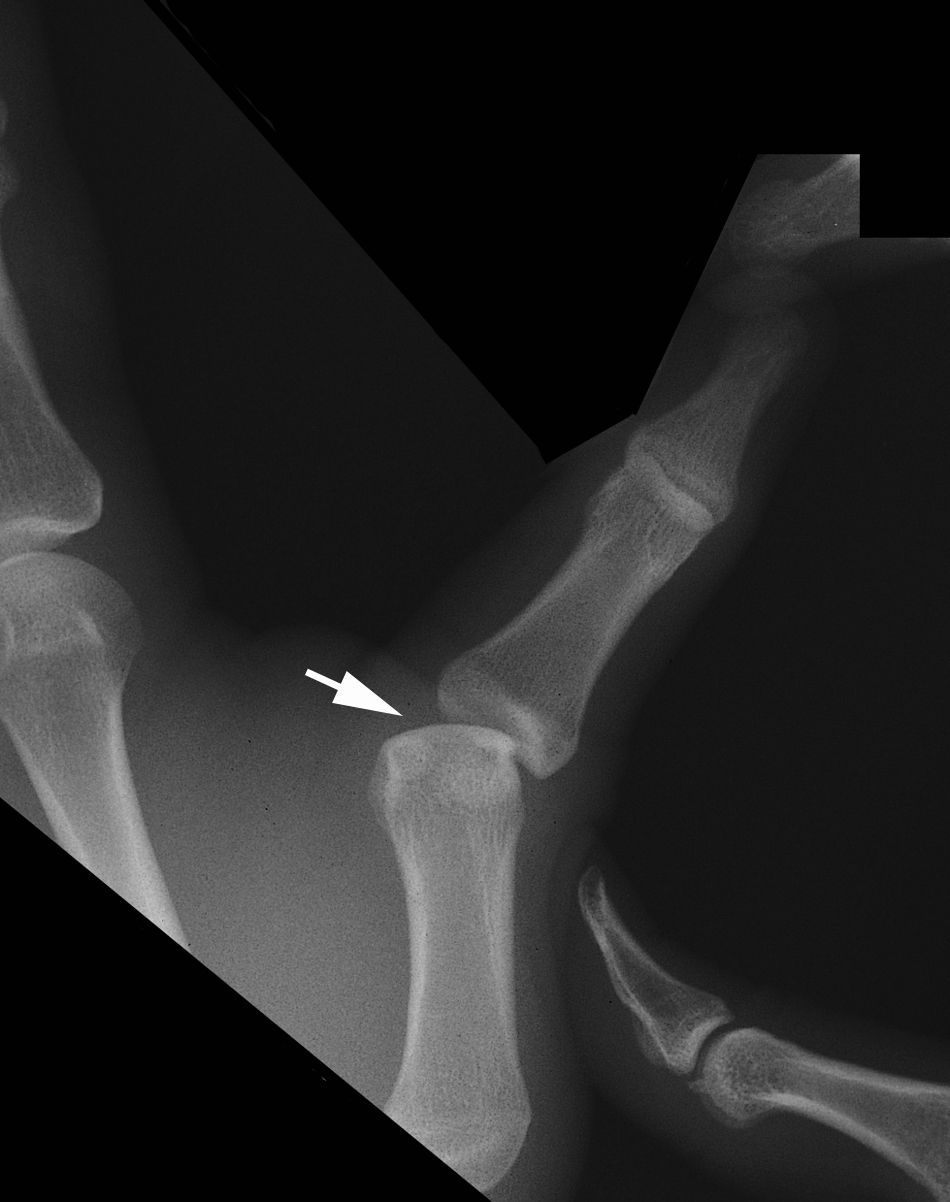

Stress x-ray of MCP joint

Stress X-ray showing an unstable MCP joint. The abnormal opening of the joint (arrow) is a sign that the ulnar collateral ligament is completely torn.

Reproduced from TR Johnson, LS Steinbach (eds.): Essentials of Musculoskeletal Imaging. Rosemont, IL. American Academy of Orthopaedic Surgeons, 2004, p. 378.